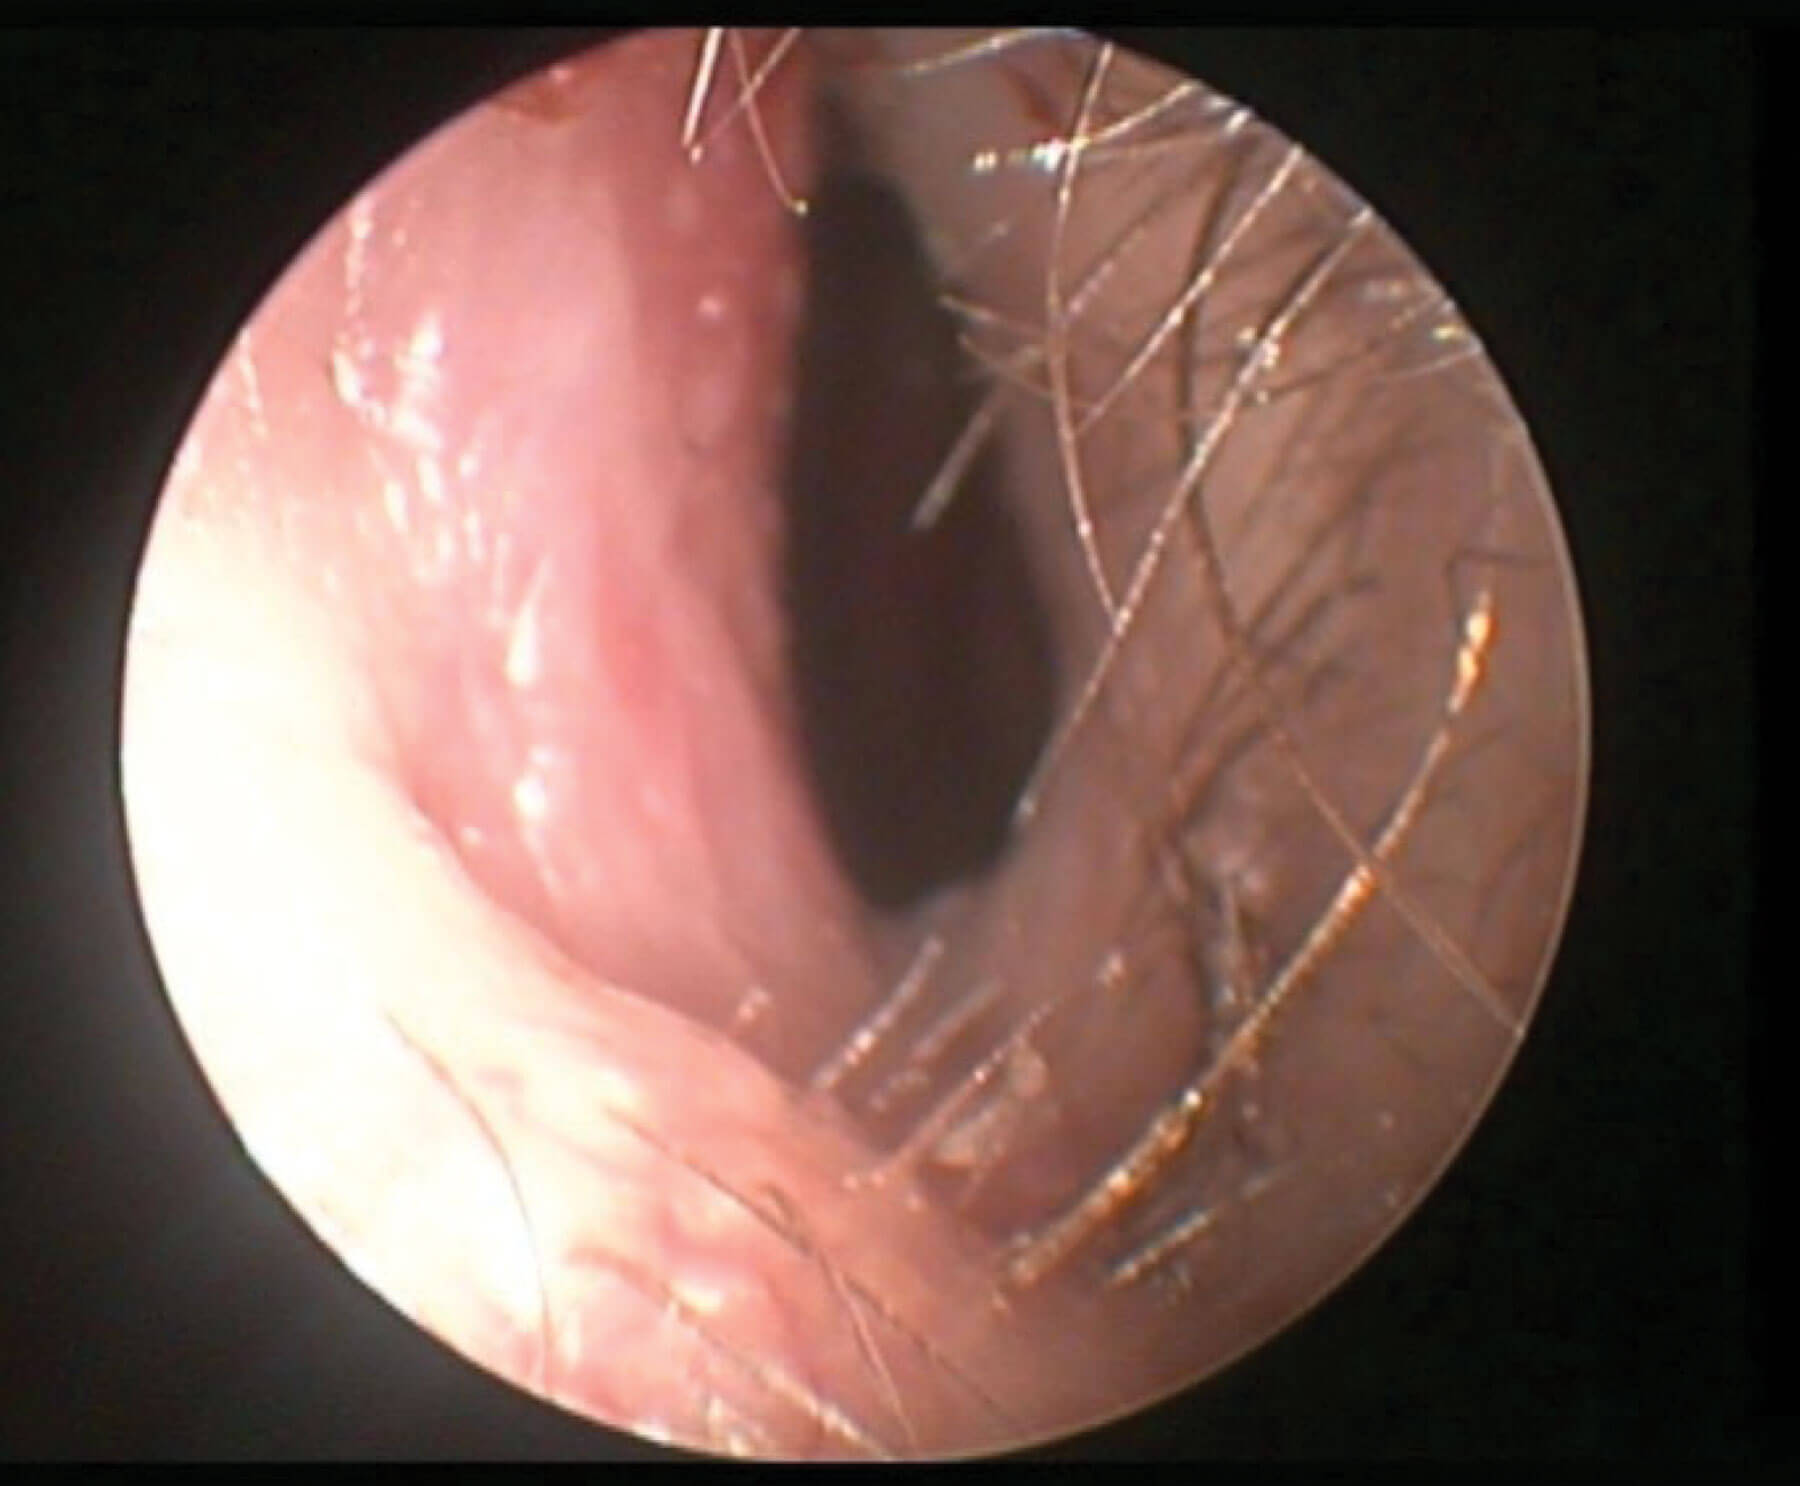

What has NAIROS taught us about septoplasty?

Septoplasty is a commonly performed procedure worldwide for nasal obstruction associated with a deviated nasal septum. In the UK, with long waiting lists for septoplasty, there is a large and unexplained variation in the incidence of this procedure between individual...